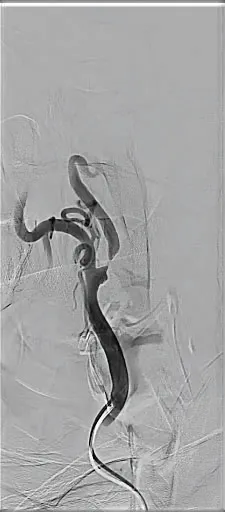

Carotid duplex ultrasound showed > 70% stenosis with a peak systolic velocity (PSV) of 438 cm/s and end-diastolic velocity (EDV) of 238 cm/s, with predominantly hypoechoic plaque (Figure 1) . This was confirmed on a CTA, which showed a type I aortic arch with tortuosity of the innominate artery, a critical proximal right ICA stenosis, and severe tortuosity of the mid to distal ICA.

Figure 1. The carotid duplex images showing > 70% stenosis with a PSV of 438 cm/s and EDV of 238 cm/s with predominantly hypoechoic plaque.